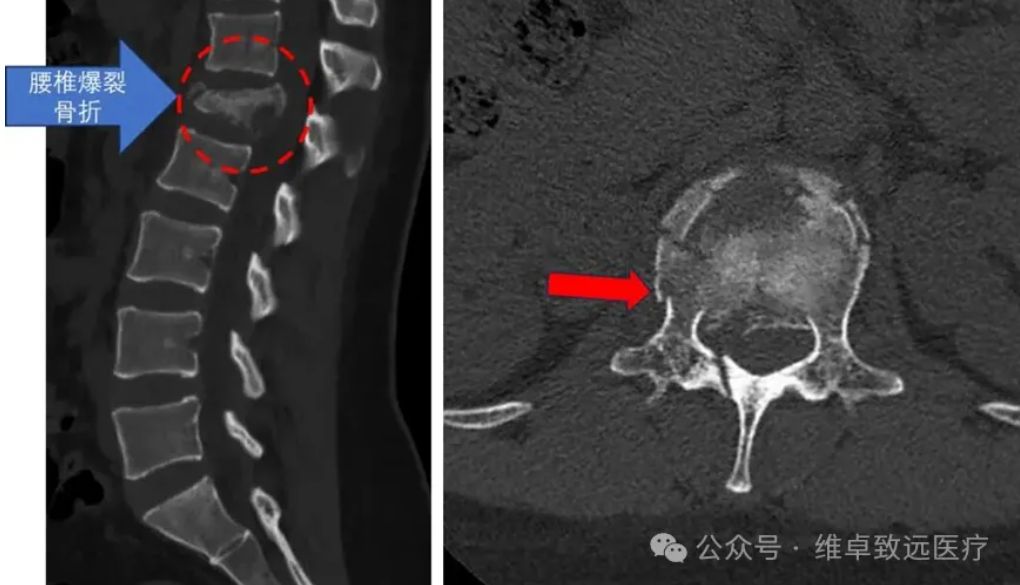

危急病情: 高坠致椎体爆裂骨折,神经受压命悬一线 术前X光:提示腰1椎体爆裂骨折 患者林女士(化名),29岁,因意外从近十米高处坠落,当即出现腰背部剧烈疼痛伴右下肢放射痛,被家人紧急送至广东医科大学附属医院脊柱外科二区就诊。 入院后,脊柱相关影像学检查结果显示:患者腰1椎体爆裂性骨折,部分碎裂骨块向后突入椎管,导致椎管明显狭窄,后方脊神经受到直接压迫。 术前 MRI: 提示有游离骨块向后移位压迫神经, 椎管容积明显变小 据主治医生介绍,该患者病情危急且复杂:不仅椎体及附件粉碎严重,存在骨折块移位刺激神经的情况,左侧椎弓根更出现断裂,传统手术中精准置入椎弓根螺钉的难度极大。若手术操作不当,可能导致永久性神经损伤、下肢瘫痪等严重后果,对手术的精准度和安全性提出了极致要求。 术前 CT: 提示腰 1 椎体爆裂骨折,右侧椎弓根断裂 (图中红色箭头所示) 技术革新: 星航导航系统,构建全流程数字化手术平台 传统脊柱内固定手术中,尤其是面对骨折粉碎、解剖结构异常的复杂病例时,椎弓根螺钉的置入往往依赖医生的临床经验和术中X光片的反复透视,如同“盲人摸象”,不仅存在置钉位置不佳的风险,还可能损伤神经血管,且术中辐射暴露较多。 为突破这一技术瓶颈,广东医科大学附属医院前瞻性引进由维卓致远创新研发的星航骨科手术导航系统。该系统由中国工程院唐佩福院士牵头,汇聚顶尖骨科专家与工程师智慧,历时四年研制而成,已斩获多项国家发明专利及创新医疗器械认证。 其核心优势并非单一导航功能,而是构建了“影像交互-手术规划-精准导航” 的全流程数字化手术平台,通过底层技术融合,系统性提升脊柱外科疑难重症的诊疗能力,彰显了我院紧跟医疗科技前沿的战略眼光。 精准手术: 手术规划 + 实时导航,实现 “所见即所得” 维卓致远导航系统手术规划 本次手术的核心技术亮点在于星航导航系统 “打破时空限制” 的精准导航能力。术前,林颢教授带领医疗团队将患者腰椎CT数据导入系统,利用其手术规划模块,在三维模型上自动识别骨折椎体,精准规划每颗螺钉的最佳植入路径、直径及长度,并从数字耗材库中预选匹配螺钉进行模拟植入,形成个性化 “数字手术蓝图”。 与传统导航需依赖昂贵笨重的术中三维扫描设备(如O型臂)重新获取影像匹配不同,星航导航采用多模态配准技术,直接将术前三维CT规划与术中普通二维X光片精准匹配,实现三维术中导航,如同为手术视野加载“GPS定位”与“实时透视”功能。医生可在导航屏幕上实时查看虚拟螺钉路径与实际解剖结构的完美叠加,真正实现“所见即所得”的精准操作。 12月9日,在充分术前准备后,手术正式启动。在星航导航系统的实时引导下,林颢教授凭借二十余年丰富的手术经验,娴熟完成导针置入、开路、螺钉固定等操作,每一步都精准避开重要神经和血管。 整个置钉过程流畅高效,不仅大幅减少术中透视次数、降低辐射暴露,更确保了内固定的最佳生物力学稳定性。术后复查显示,所有椎弓根螺钉位置精准,骨折复位满意,椎管容积有效恢复,患者神经压迫症状迅速缓解,目前恢复状况良好。 术后复查:椎弓根螺钉位置完美,骨折复位良好 专家解读: 技术赋能,开启脊柱外科精准治疗新时代 骨科中心主任、脊柱外科专家魏劲松教授表示:“对于林女士这类复杂爆裂性骨折病例,椎弓根置钉的容错率极低。星航导航系统提供的毫米级精准指引,显著提升了手术安全性与疗效可预期性。此次成功实践,不仅为我们开展更复杂的脊柱畸形矫正、微创手术积累了宝贵经验,更为科室临床技术创新与科研发展开辟了新思路。” 林颢教授强调,星航导航系统的成功应用,是骨科手术从“经验依赖”向“数据驱动、精准可视”转型的重要里程碑。其术前规划让手术方案更优化,术中多模态配准技术则破解了传统导航对昂贵设备的依赖难题,真正实现精准、微创、高效的诊疗目标,对患者、医生与医院均具有重大意义。” 左二为林颢(主刀手术中) 作为粤西地区医疗高地,广东医科大学附属医院始终勇于拥抱医疗科技前沿,持续提升诊疗服务水平。此次粤西首例星航骨科导航系统辅助脊柱手术的成功开展,是医院技术创新与学科建设的又一重要成果。 未来,医院将继续探索推广数字化智能手术技术,让更多医疗创新成果惠及广大患者,为推动骨科手术精准化、微创化、智能化发展贡献 “附院力量”。